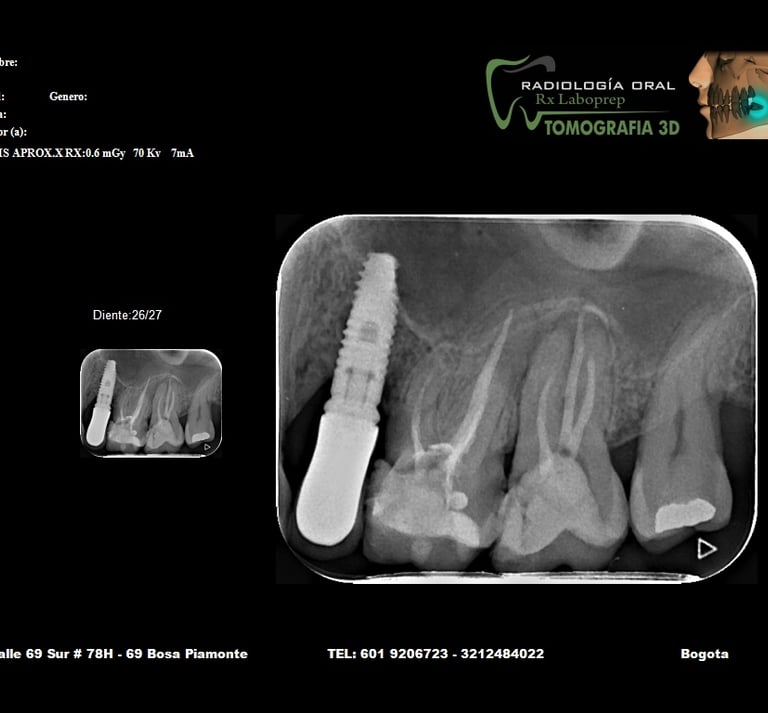

Imágenes de nuestros servicios radiológicos.